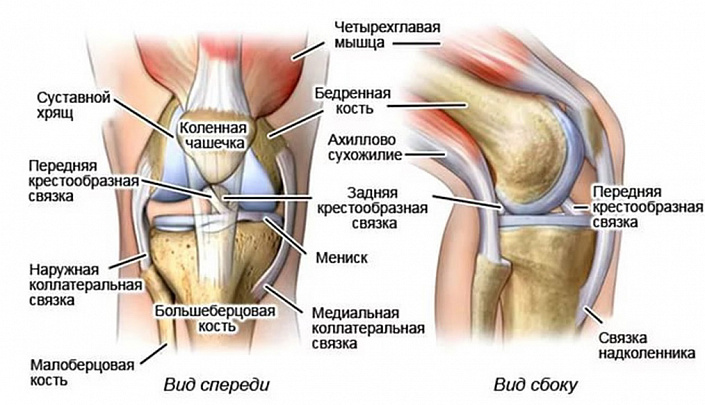

В состав колена входят три кости:

- Бедренная. Она присоединяется к суставу дистальным концом и выполняет функцию своеобразной опоры ноги.

- Большеберцовая. Эта трубчатая кость примыкает к колену проксимальным концом и отвечает в первую очередь за подвижность конечности.

- Надколенник, или коленная чашечка. Самая крупная сесамовидная кость человеческого организма оберегает коленный сустав от возможных травм, возникших вследствие бокового смещения (например, при неудачном вывихе, подворачивании ноги и других подобных травмах).

Снизу анатомия колена представлена хрящевыми мыщелками, которые соприкасаются с поверхностью большеберцового плато, способствуя правильному формированию особого углубления. Именно это углубление является ключевым звеном в механизме сгибания и разгибания коленного сустава.

Связки, расположенные в области коленного сочленения, представлены следующими группами:

- боковые — коллатеральная мало- и большеберцовая;

- задние — надколенника, поддерживающая медиальная и латеральная, подколенная, дугообразная;

- внутрисуставные — поперечная и две крестообразные.

Несмотря на то, что каждая из этих групп по-своему функциональна и незаменима, наибольшее значение для подвижности сустава имеют крестообразные связки — передняя и задняя. Передние крестообразные связочные волокна удерживают коленный сустав, фиксируют наружный мыщелок поверхности большеберцовой кости и препятствуют излишнему смещению голени вперед, что, в свою очередь, позволяет защитить сустав от серьёзной травмы. Задняя связка, напротив, ограничивает смещение голени назад и прикрепляется к задней мыщелковой ямке. Такой баланс позволяет обеспечить разумное физиологичное вращение коленного сустава, предотвратив при этом патологическую подвижность.